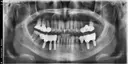

상담원분이 친절하시고 너무 좋았어요! 임플란트 어디서 해야하나 많이 고민했는데 가격도 저렴하니 좋더라구요~ 엘베가 느린건지 타는 사람인지 많은건지 모르겠지만 병원 들어갈때 오래 걸리는 느낌이라 더 긴장되고ㅜㅜ 임플란트가 처음이라 너무 걱정됐는데 괜한 걱정했네요🤭 원장님이랑 간호사분들 너무 친절하셨어요! 과잉진료 이런것도 전혀 없으시구 꼼꼼하니 잘된것 같아서 만족합니다❤️🔥